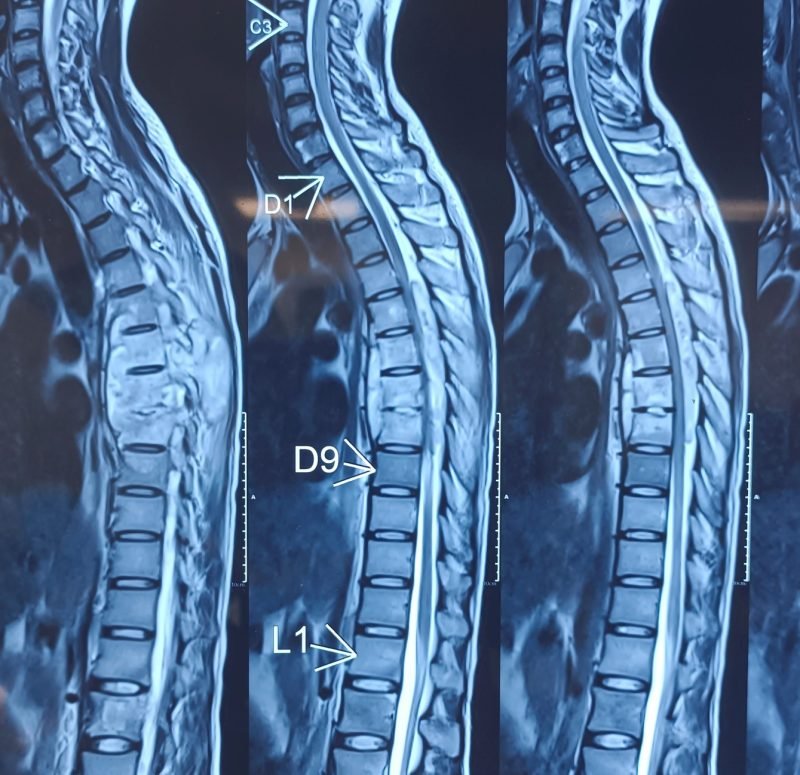

Severe spinal infection causing significant spinal cord compression along with prevertebral and paravertebral abscess formation.

Weakness in both legs, difficulty walking, and possible bladder control problems.

Spinal fixation and decompression surgery including laminectomy, abscess drainage, and biopsy to relieve pressure and control infection.